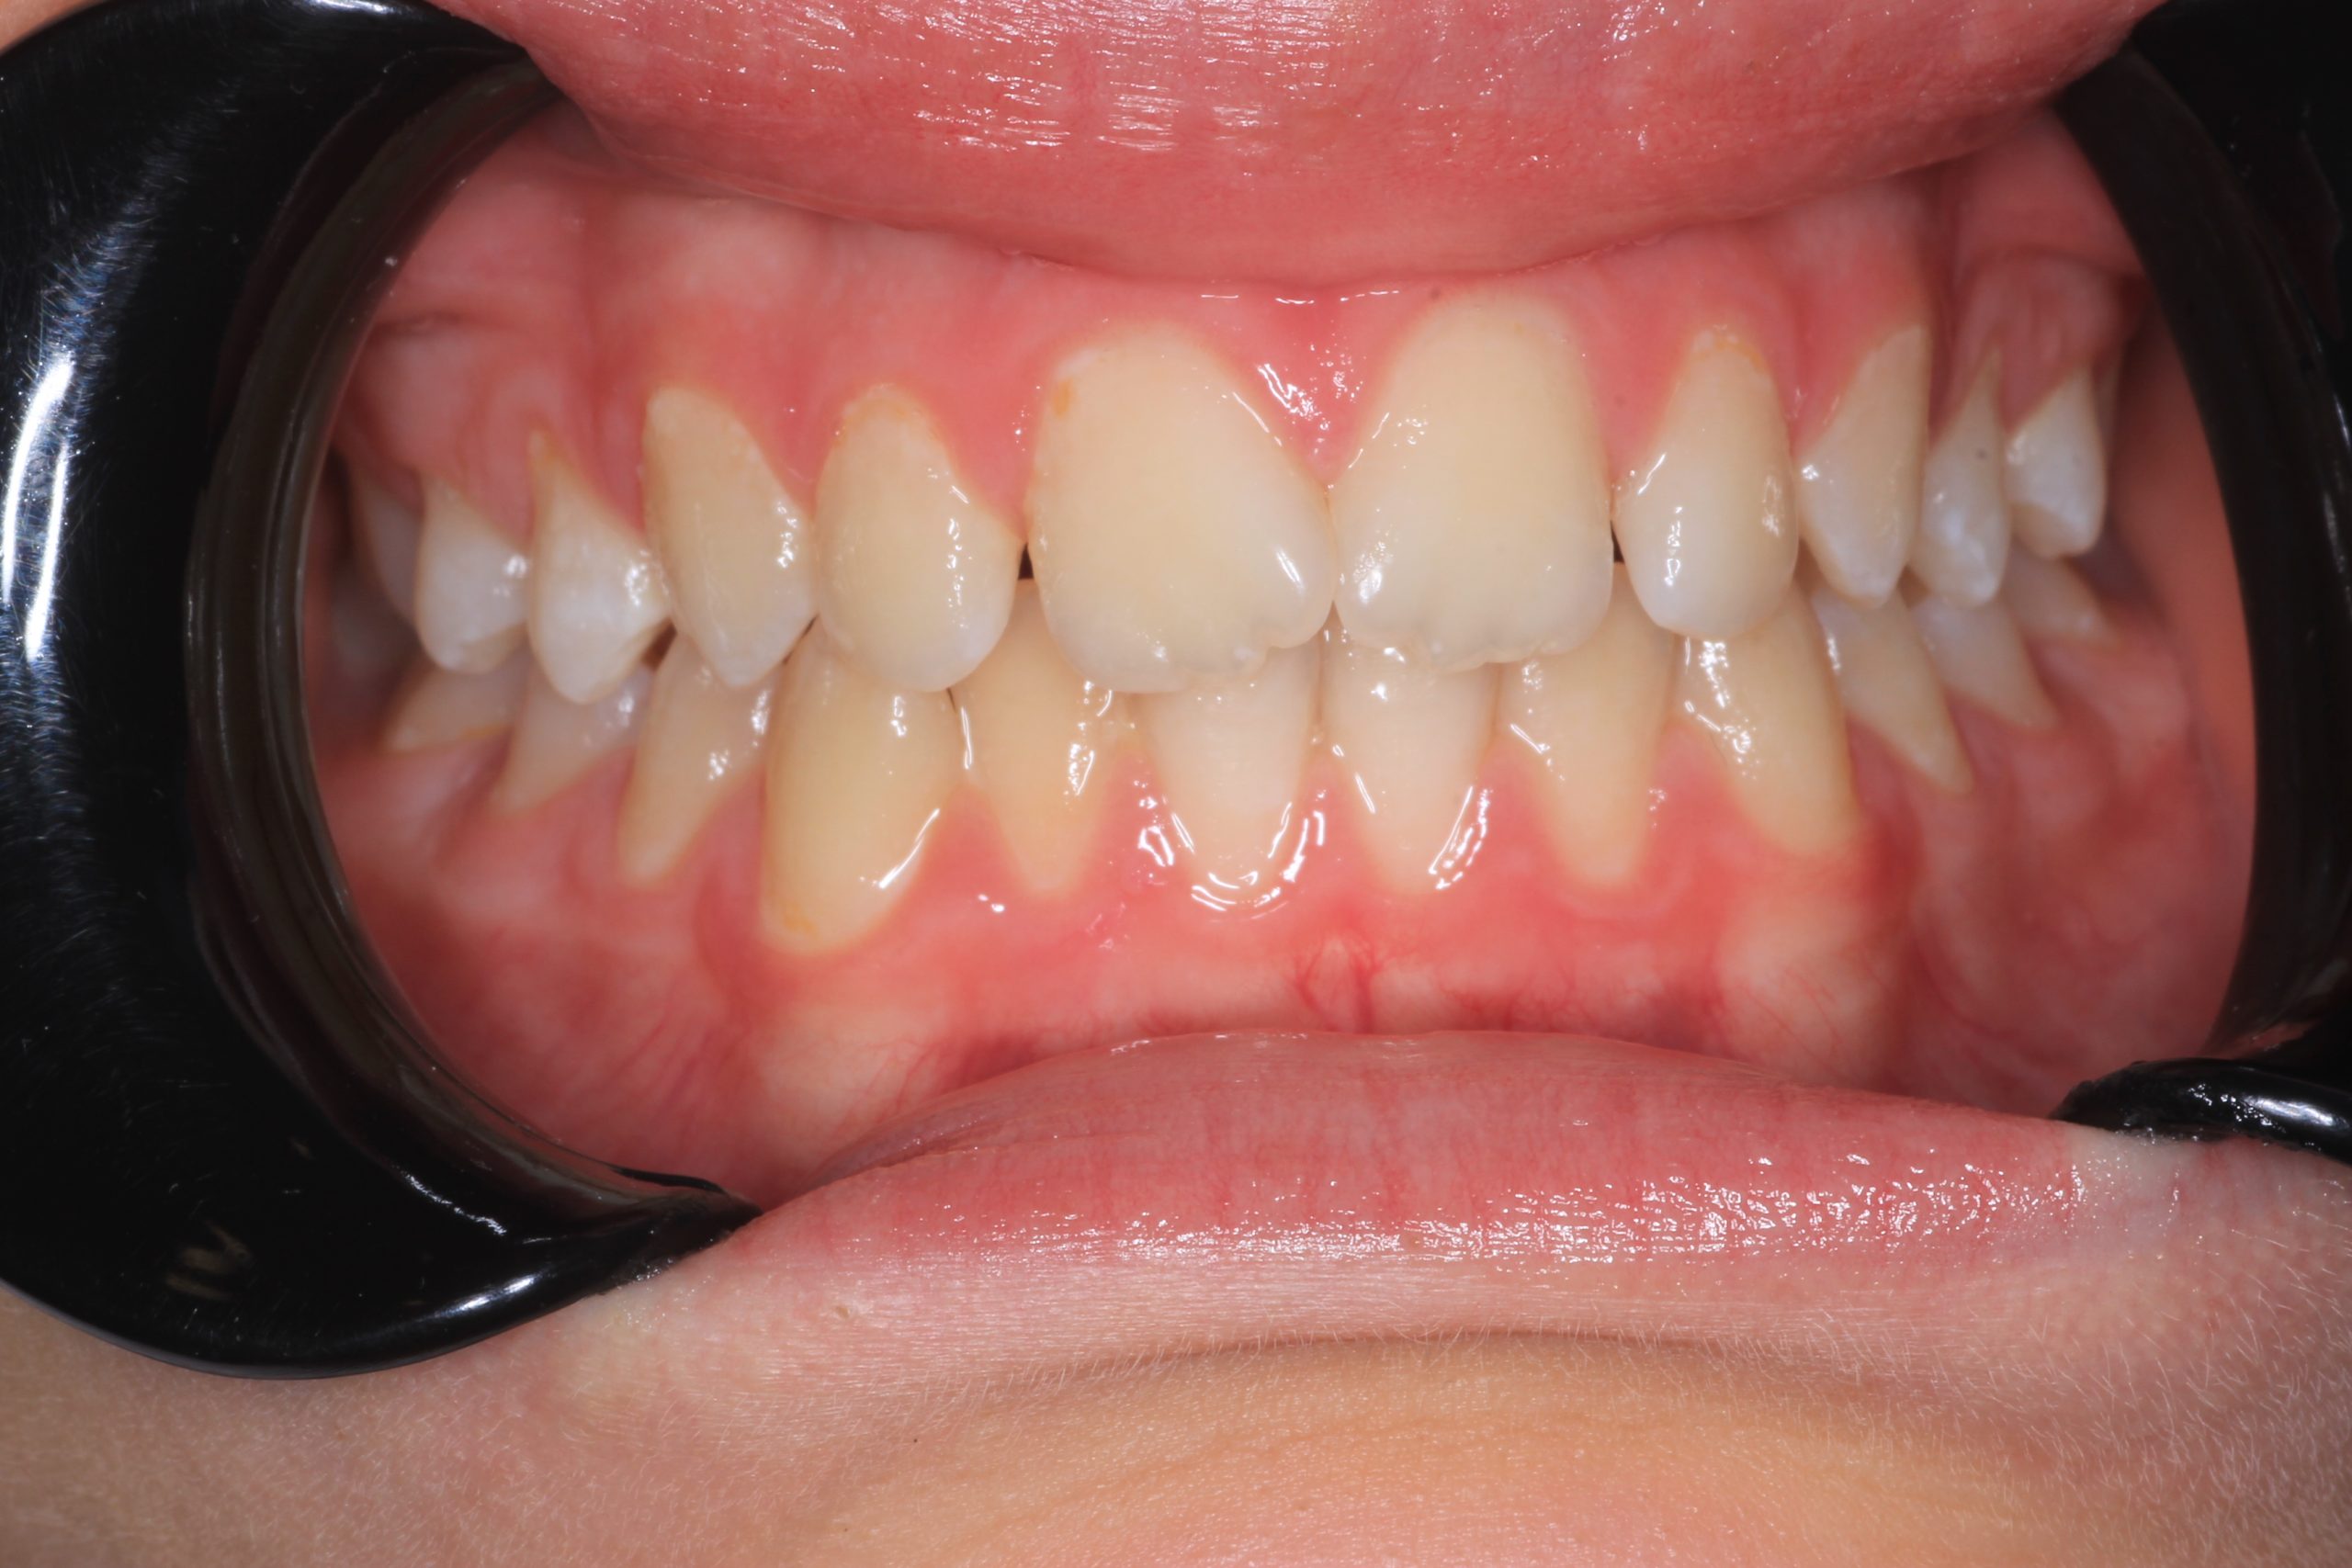

- Detailed Examination

We examine the condition of teeth, gums, and bite. - Plaque Disclosure with Special Indicators